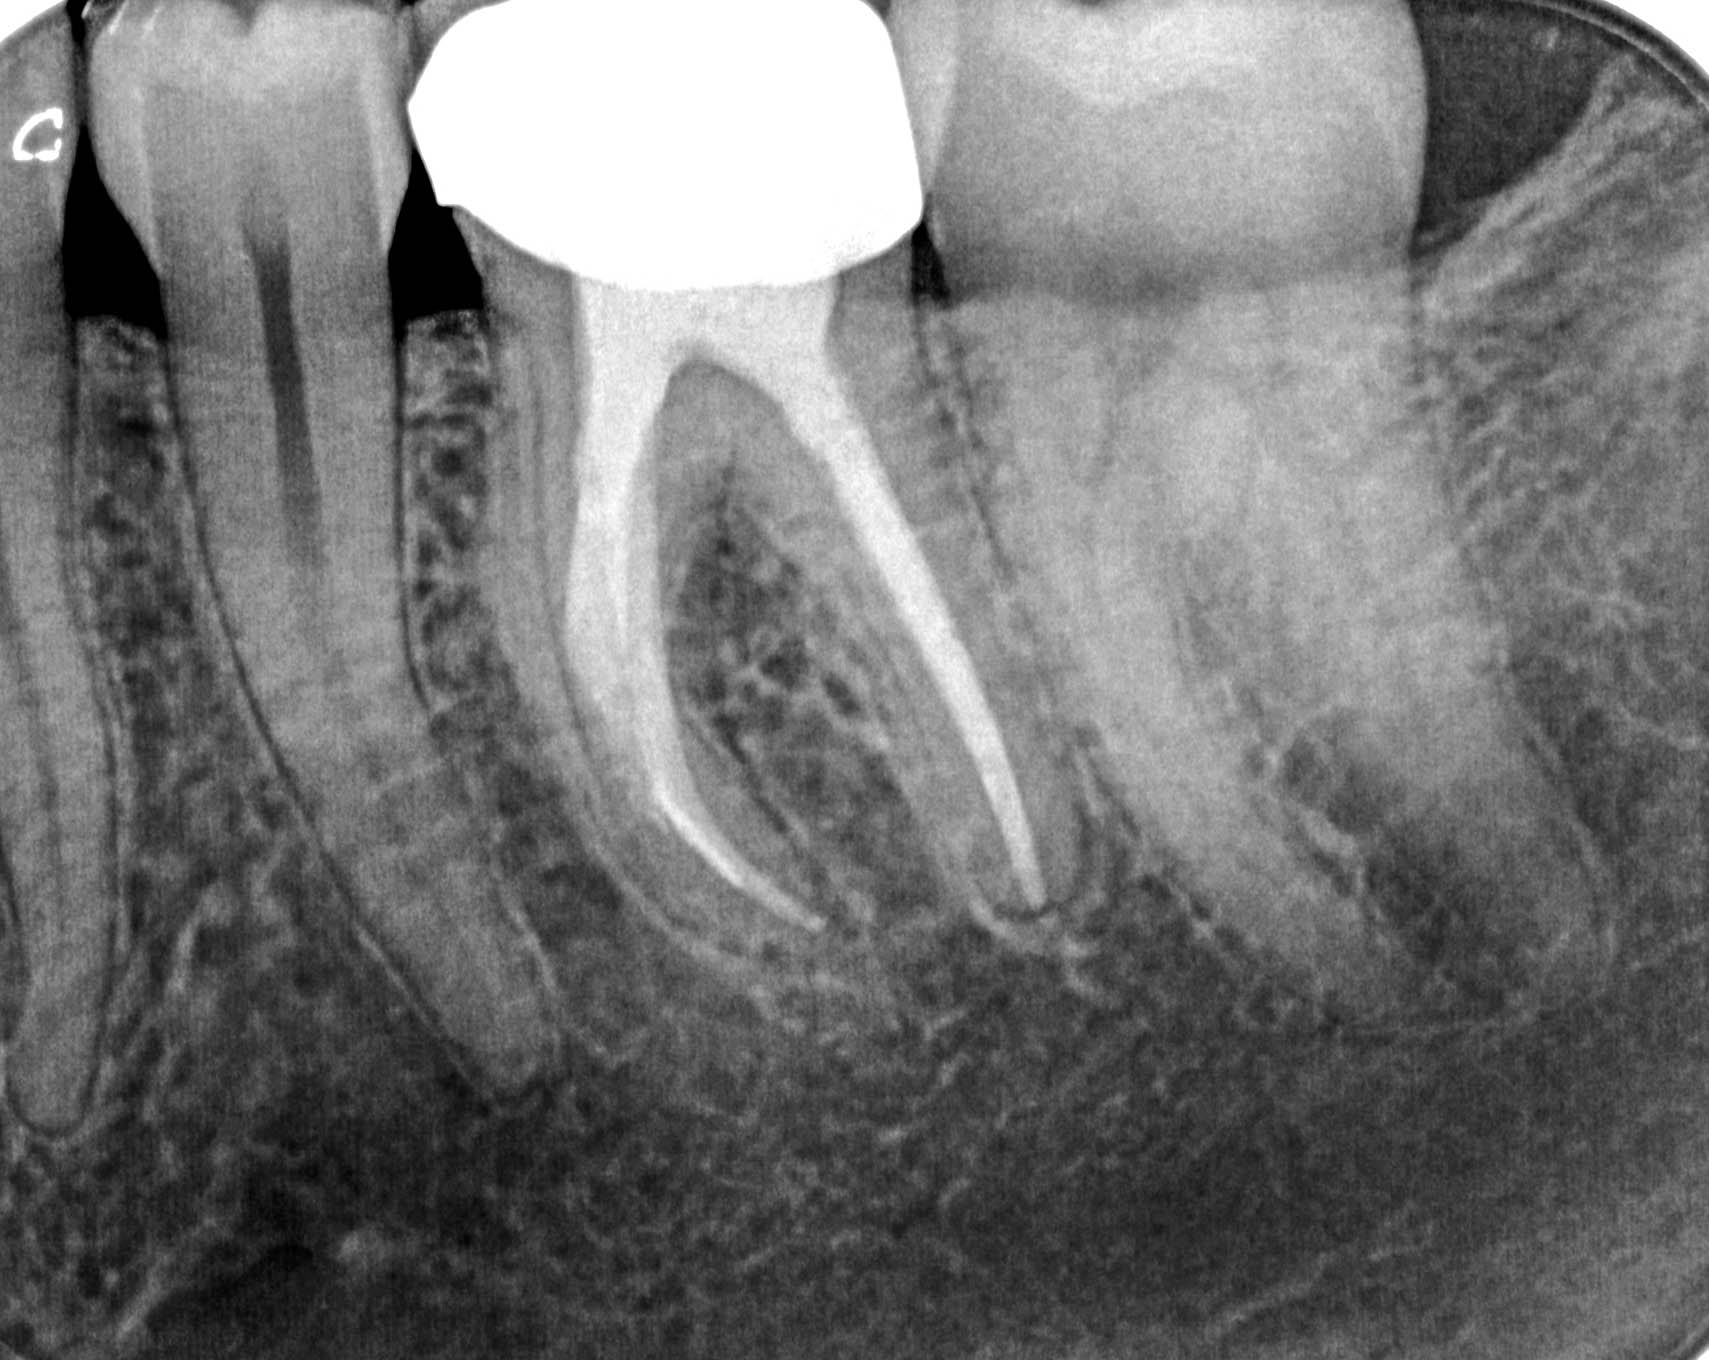

RRK (1 von 1)-15

Calciumhydroxid – Überpressung (1)